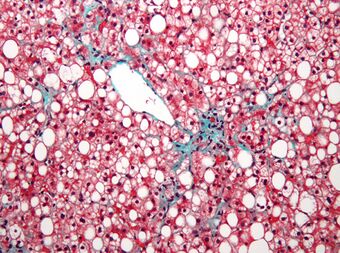

| Micrograph showing a fatty liver (macrovesicular steatosis), as seen in non-alcoholic fatty liver disease. Trichrome stain. |

The fatty change represents the intracytoplasmatic accumulation of triglycerides (neutral fats). At the beginning, the hepatocytes present small fat vacuoles (liposomes) around the nucleus (microvesicular fatty change). In this stage, liver cells are filled with multiple fat droplets that do not displace the centrally located nucleus. In the late stages, the size of the vacuoles increases, pushing the nucleus to the periphery of the cell, giving a characteristic signet ring appearance (macrovesicular fatty change). These vesicles are well-delineated and optically "empty" because fats dissolve during tissue processing. Large vacuoles may coalesce and produce fatty cysts, which are irreversible lesions. Macrovesicular steatosis is the most common form and is typically associated with alcohol, diabetes, obesity, and corticosteroids. Acute fatty liver of pregnancy and Reye's syndrome are examples of severe liver disease caused by microvesicular fatty change.[19] The diagnosis of steatosis is made when fat in the liver exceeds 5–10% by weight.[13][20][21]